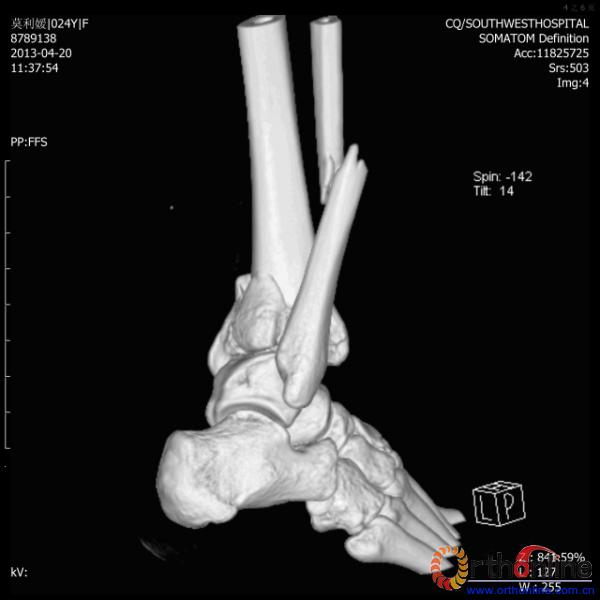

伤员和家属迅速赶到西南医院,10点关节外科段小军副教授查看伤员后急诊收入院,拍摄X片和急诊行三维CT重建检查,提示踝关节创伤严重,出现三踝骨折伴胫距关节脱位,需要急诊手术治疗。随后段教授与正在四川成都参加“汶川地震5周年灾害医学救治研讨会”的杨柳主任联系,进一步完善救治方案。地震当晚,段教授为该伤员进行急诊手术,手术顺利对复杂骨折进行了解剖复位,有效的钢板螺钉固定。术后伤员的疼痛明显缓解,复查X片,踝关节结构恢复满意。

患者术前CT(二)